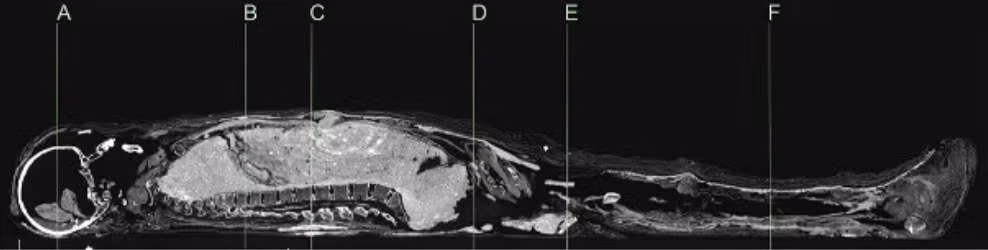

Các nhà khoa học Australia mới tiến hành chụp CT và xác định niên đại bằng phương pháp carbon phóng xạ cho một xác ướp Ai Cập và cỗ quan tài. Hiện chúng được lưu giữ và bảo quản tại Đại học Sydney.

Kết quả kiểm tra cho thấy xác ướp người phụ nữ có niên đại vào khoảng năm 1200 trước Công nguyên.

Trong khi đó, chiếc quan tài chứa xác ướp có niên đại vào khoảng năm 1000 trước Công nguyên.

Điều này đồng nghĩa với việc chiếc quan tài và xác ướp có niên đại không trùng khớp. Thi hài người phụ nữ có niên đại lớn hơn cỗ quan tài khoảng 200 năm.

Xác ướp người phụ nữ này được bọc trong một lớp bùn. Kỹ thuật này được cho là bắt chước theo phong tục mai táng của hoàng gia Ai Cập thời cổ đại.